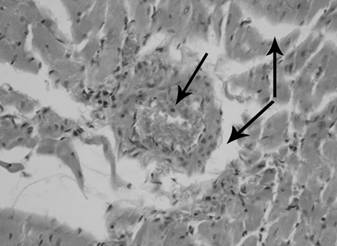

Результаты гистологического исследования миокарда указывают на то, что через 12 часов после реваскуляризации конечностей отмечаются следующие нарушения периферического кровообращения: полнокровие вен и артерий, сосудов микроциркуляторного русла с расширением их просветов и истончением стенок; явления стаза и сладжа, при котором наблюдали агрегацию эритроцитов в виде "монетных столбиков". Повышенная проницаемость сосудистой стенки проявляется набуханием эндотелия, гомогенизацией отдельных сегментов и нарушением целостности стенки, а также накоплением жидкости в интерстициальной ткани с образованием периваскулярного и межуточного отека (рис. 1). Отмечаются множественные петехиальные кровоизлияния, проявляющиеся периваскулярными геморрагическими инфильтратами и локализующиеся диффузно как в субэндокардиальной и субэпикардиаьной области, так и в толще миокарда.

Рис. 1. Миокард крысы при моделировании реперфузионного синдрома через 12 часов после снятия жгутов. Артериальная гиперемия, периваскулярный и интерстициальный отек миокарда (стрелки). Окраска гематоксилином и эозином. Микрофотография. Ув. 400.